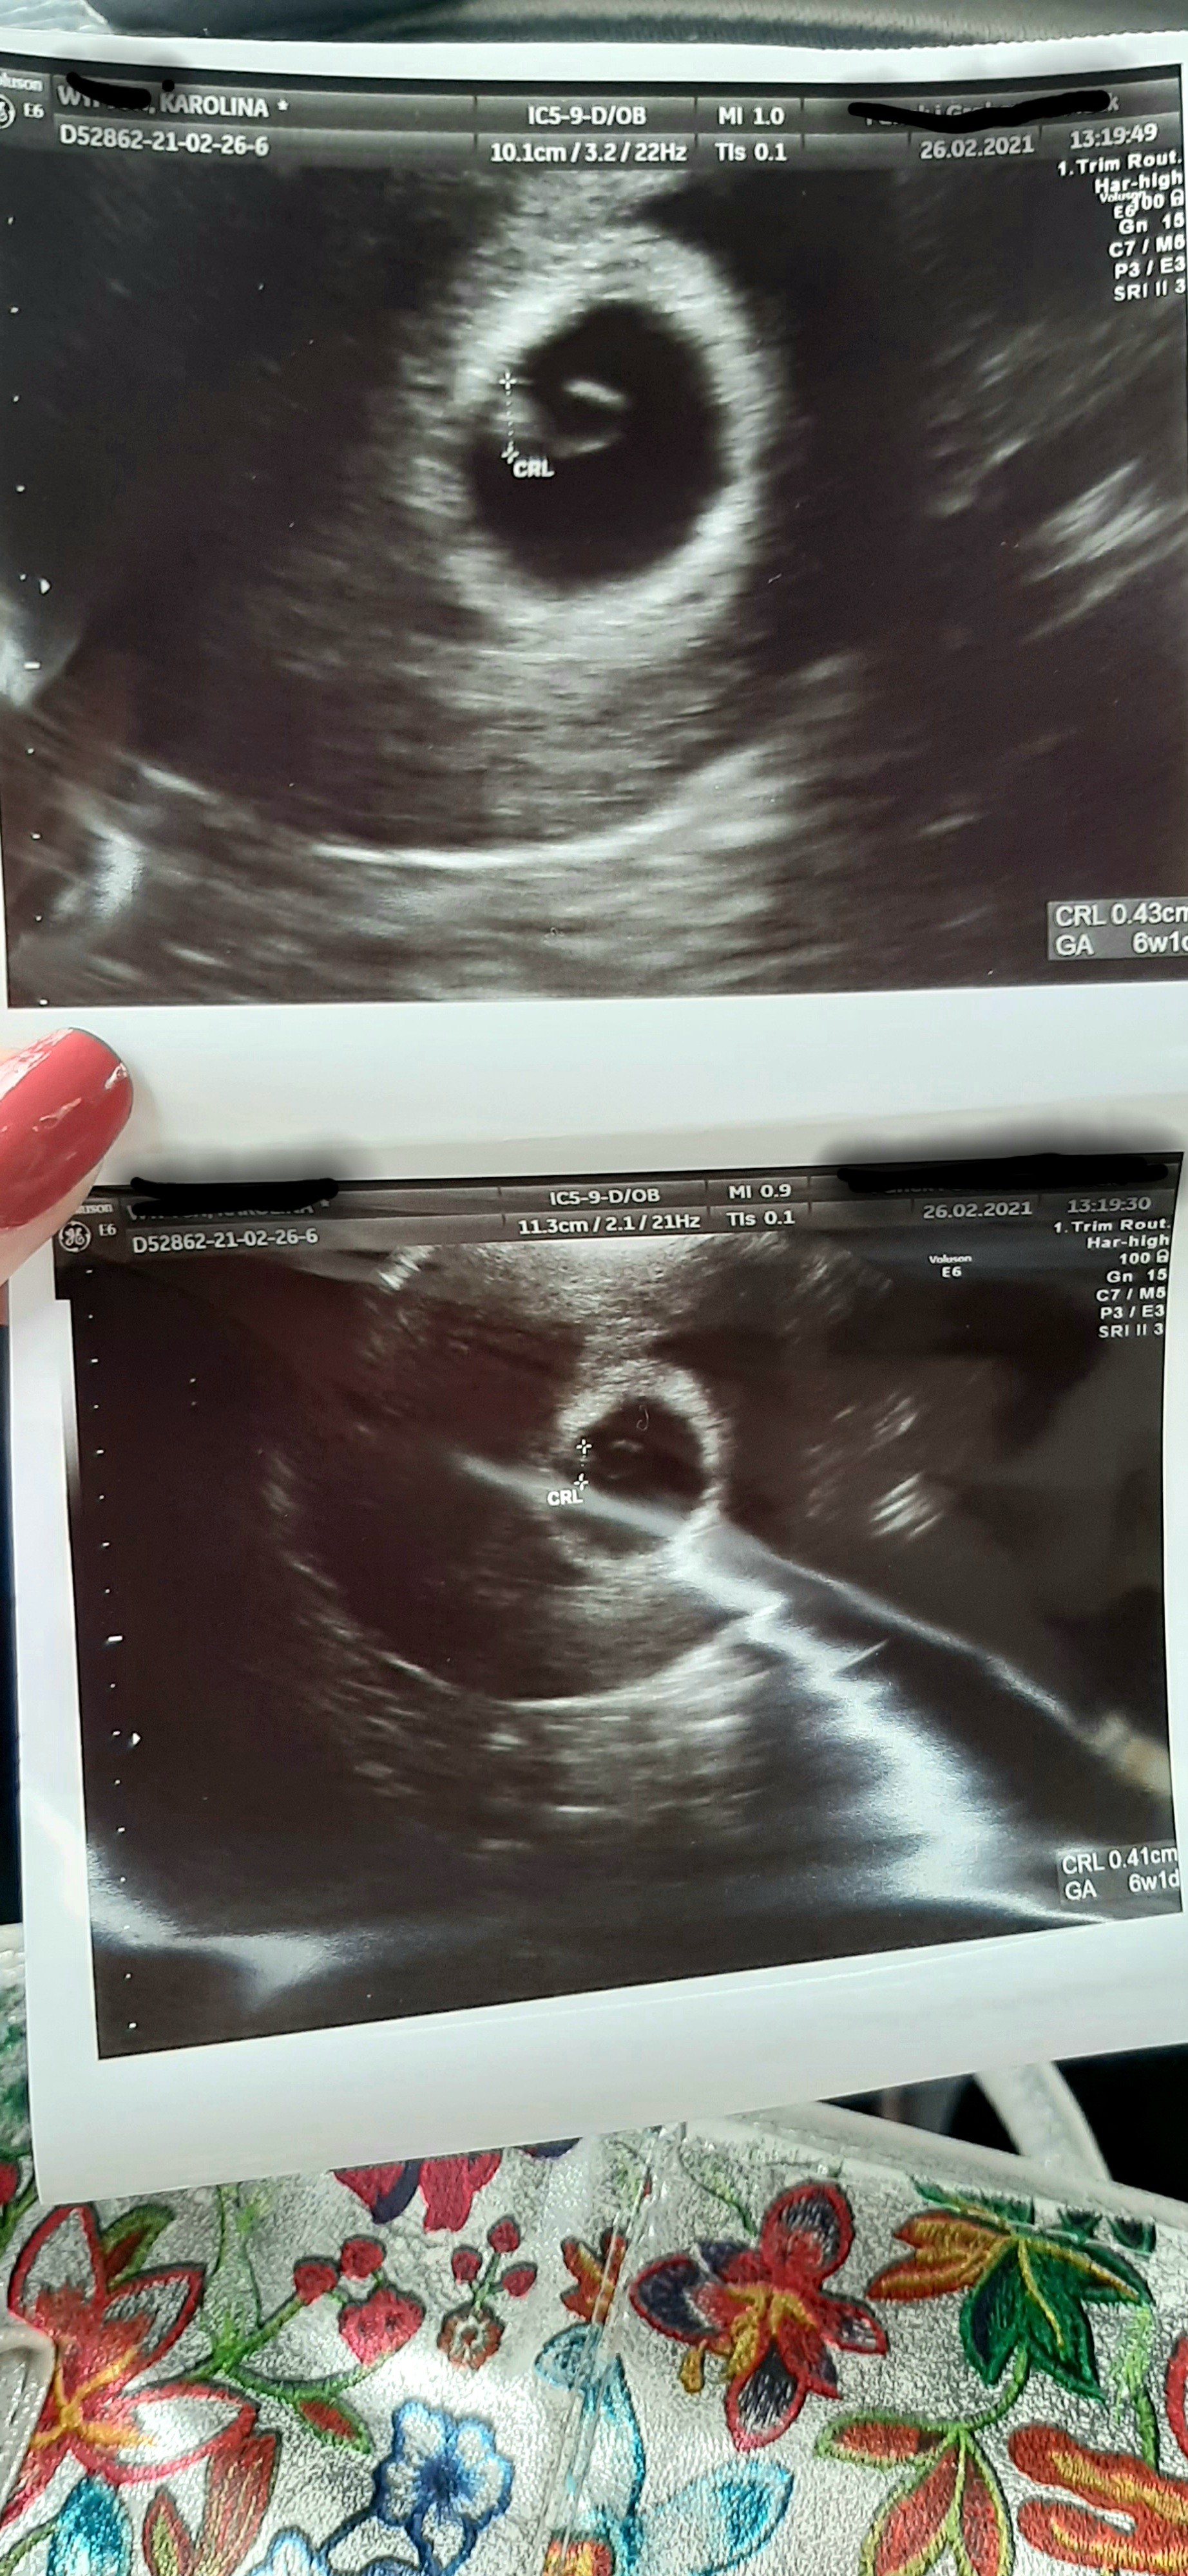

Jest serduszko Xd mam leżeć i mam znów bana na seks. Ku... Xd Zobacz załącznik 1242663